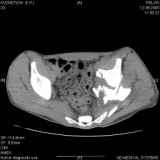

Уважаемые коллеги! Хотелось бы услышать совет по тактике лечения представлленого больного.Поступил после лечения в одном изотделений области. Травма 2,5 месяца назад. После выведенияиз шока был произведен остеосинтез перелома бедра, предплечья, до перевода к нам проводилосьвытяжение по оси шейки бедра за стержень, введенный в большой вертел. На сегодня деформацияригидна, клинически мобильности не определяется. Заранее признателен. P.S. Данный вид травм не включен в перечень "высокотехнологичных операций", направить длялечения по квотам Минздрава очень сложно.

Все-таки надо бы начать не с КТ, а с обзорного снимка таза и косых проекций впадины.

Это обзорные и косые снимки

Привет, Леонид. Оскольчатый высокий двухколонный перелом в такие сроки трогать не надо, т.к. это про такие переломы сказано: "кто с ножом на Ж. пойдет тот в ней и останется...".